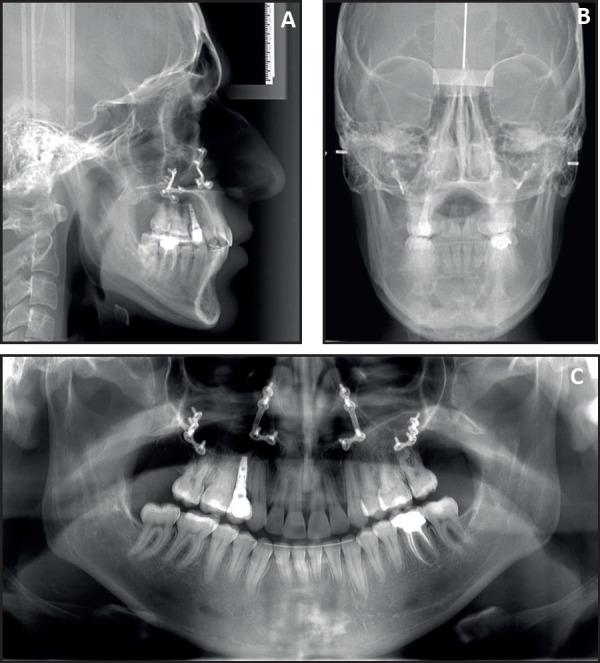

Given the complexity of the case, the treatment required a comprehensive interdisciplinary approach with the intervention of multiple specialties including periodontics, prosthodontics, orthodontics, oral surgery and maxillofacial surgery. The presurgical orthodontic stage was achieved in preparation for LeFort I maxillary advancement. Third molars extractions along with implant placement were implemented. Finally, crown placement and connective tissue graft were completed to achieve an optimal result. Total treatment time was 1.7 years (20 months). Patient's profile and facial appearance were dramatically enhanced, and a stable functional Class II occlusion was attained despite the preexisting skeletal Class III.

鉴于病例的复杂性,治疗需要综合多学科方法,包括牙周病学、修复学、正畸学、口腔颌面外科等多个专业的干预。术前正畸阶段是为上颌 LeFort I 推进做准备。实施了第三磨牙拔除和种植体植入。最后,完成了牙冠放置和结缔组织移植,以达到最佳效果。总治疗时间为 1.7 年(20 个月)。患者的侧貌和面部外观得到了显著改善,尽管存在先前的骨骼 III 类,但获得了稳定的功能性 II 类咬合。